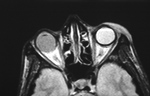

| Silicone oil in left eye |

| The oil was instilled into the left eye for treatment of retinal detachment. From Hunter, 2004 |